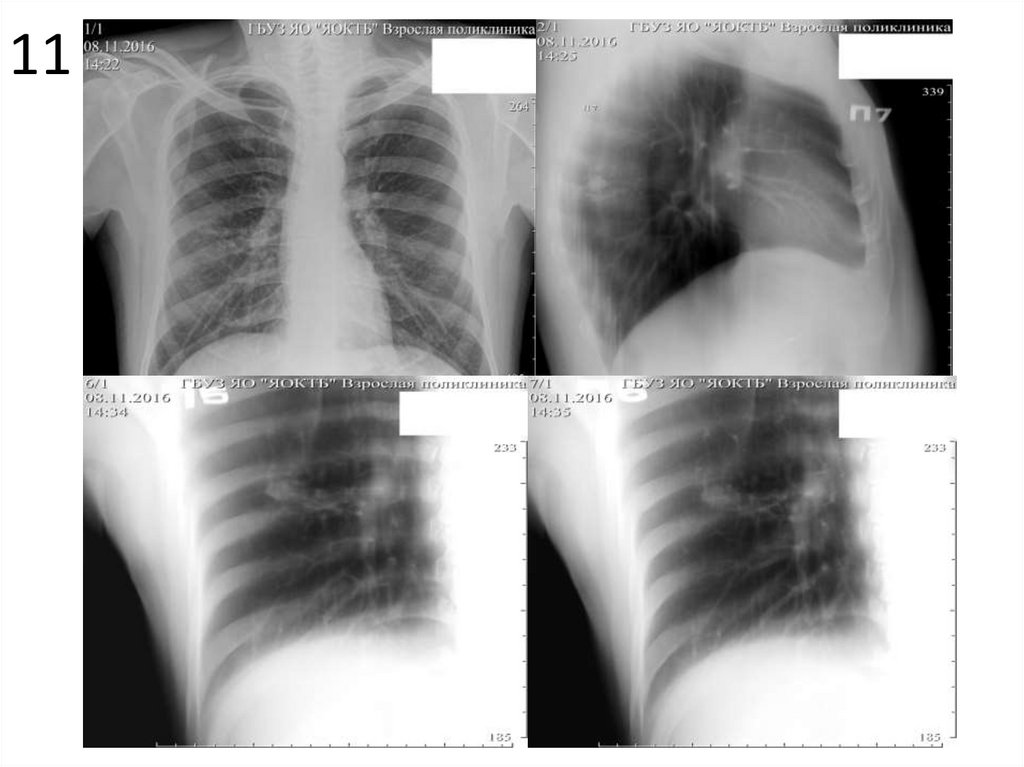

11

1. Опишите представленные снимки, выделите основной

рентгенологический синдром.

2. Имеются ли признаки туберкулеза на данных снимках?

Если да, перечислите их.

3. При наличии признаков туберкулеза определите форму,

фазу процесса, укажите возможные осложнения.